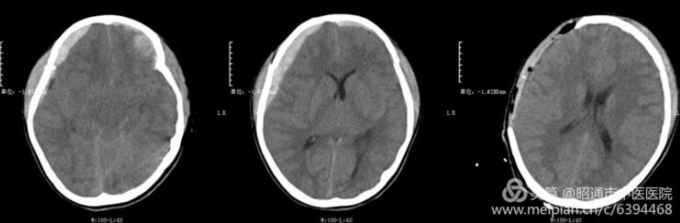

近日,一名儿童不慎从约4米高空跌落,家属及时送到我院,经检查,小孩头颅CT见少量硬膜外血肿及额叶脑挫伤,且神志清醒。翌日,由于颅内出血脑疝导致患儿突发意识障碍,神志昏迷,对光反射迟钝,随时有生命危险,肿瘤科医生立即展开术前讨论。经研究,决定立即为患儿实施硬膜外血肿清除术+去颅骨瓣减压术,住院医师凌征龙历时4个小时成功完成手术,患儿生命体征正常,神志清醒,四肢肌力正常,目前在康复治疗中。(通讯员/肿瘤科 凌征龙)